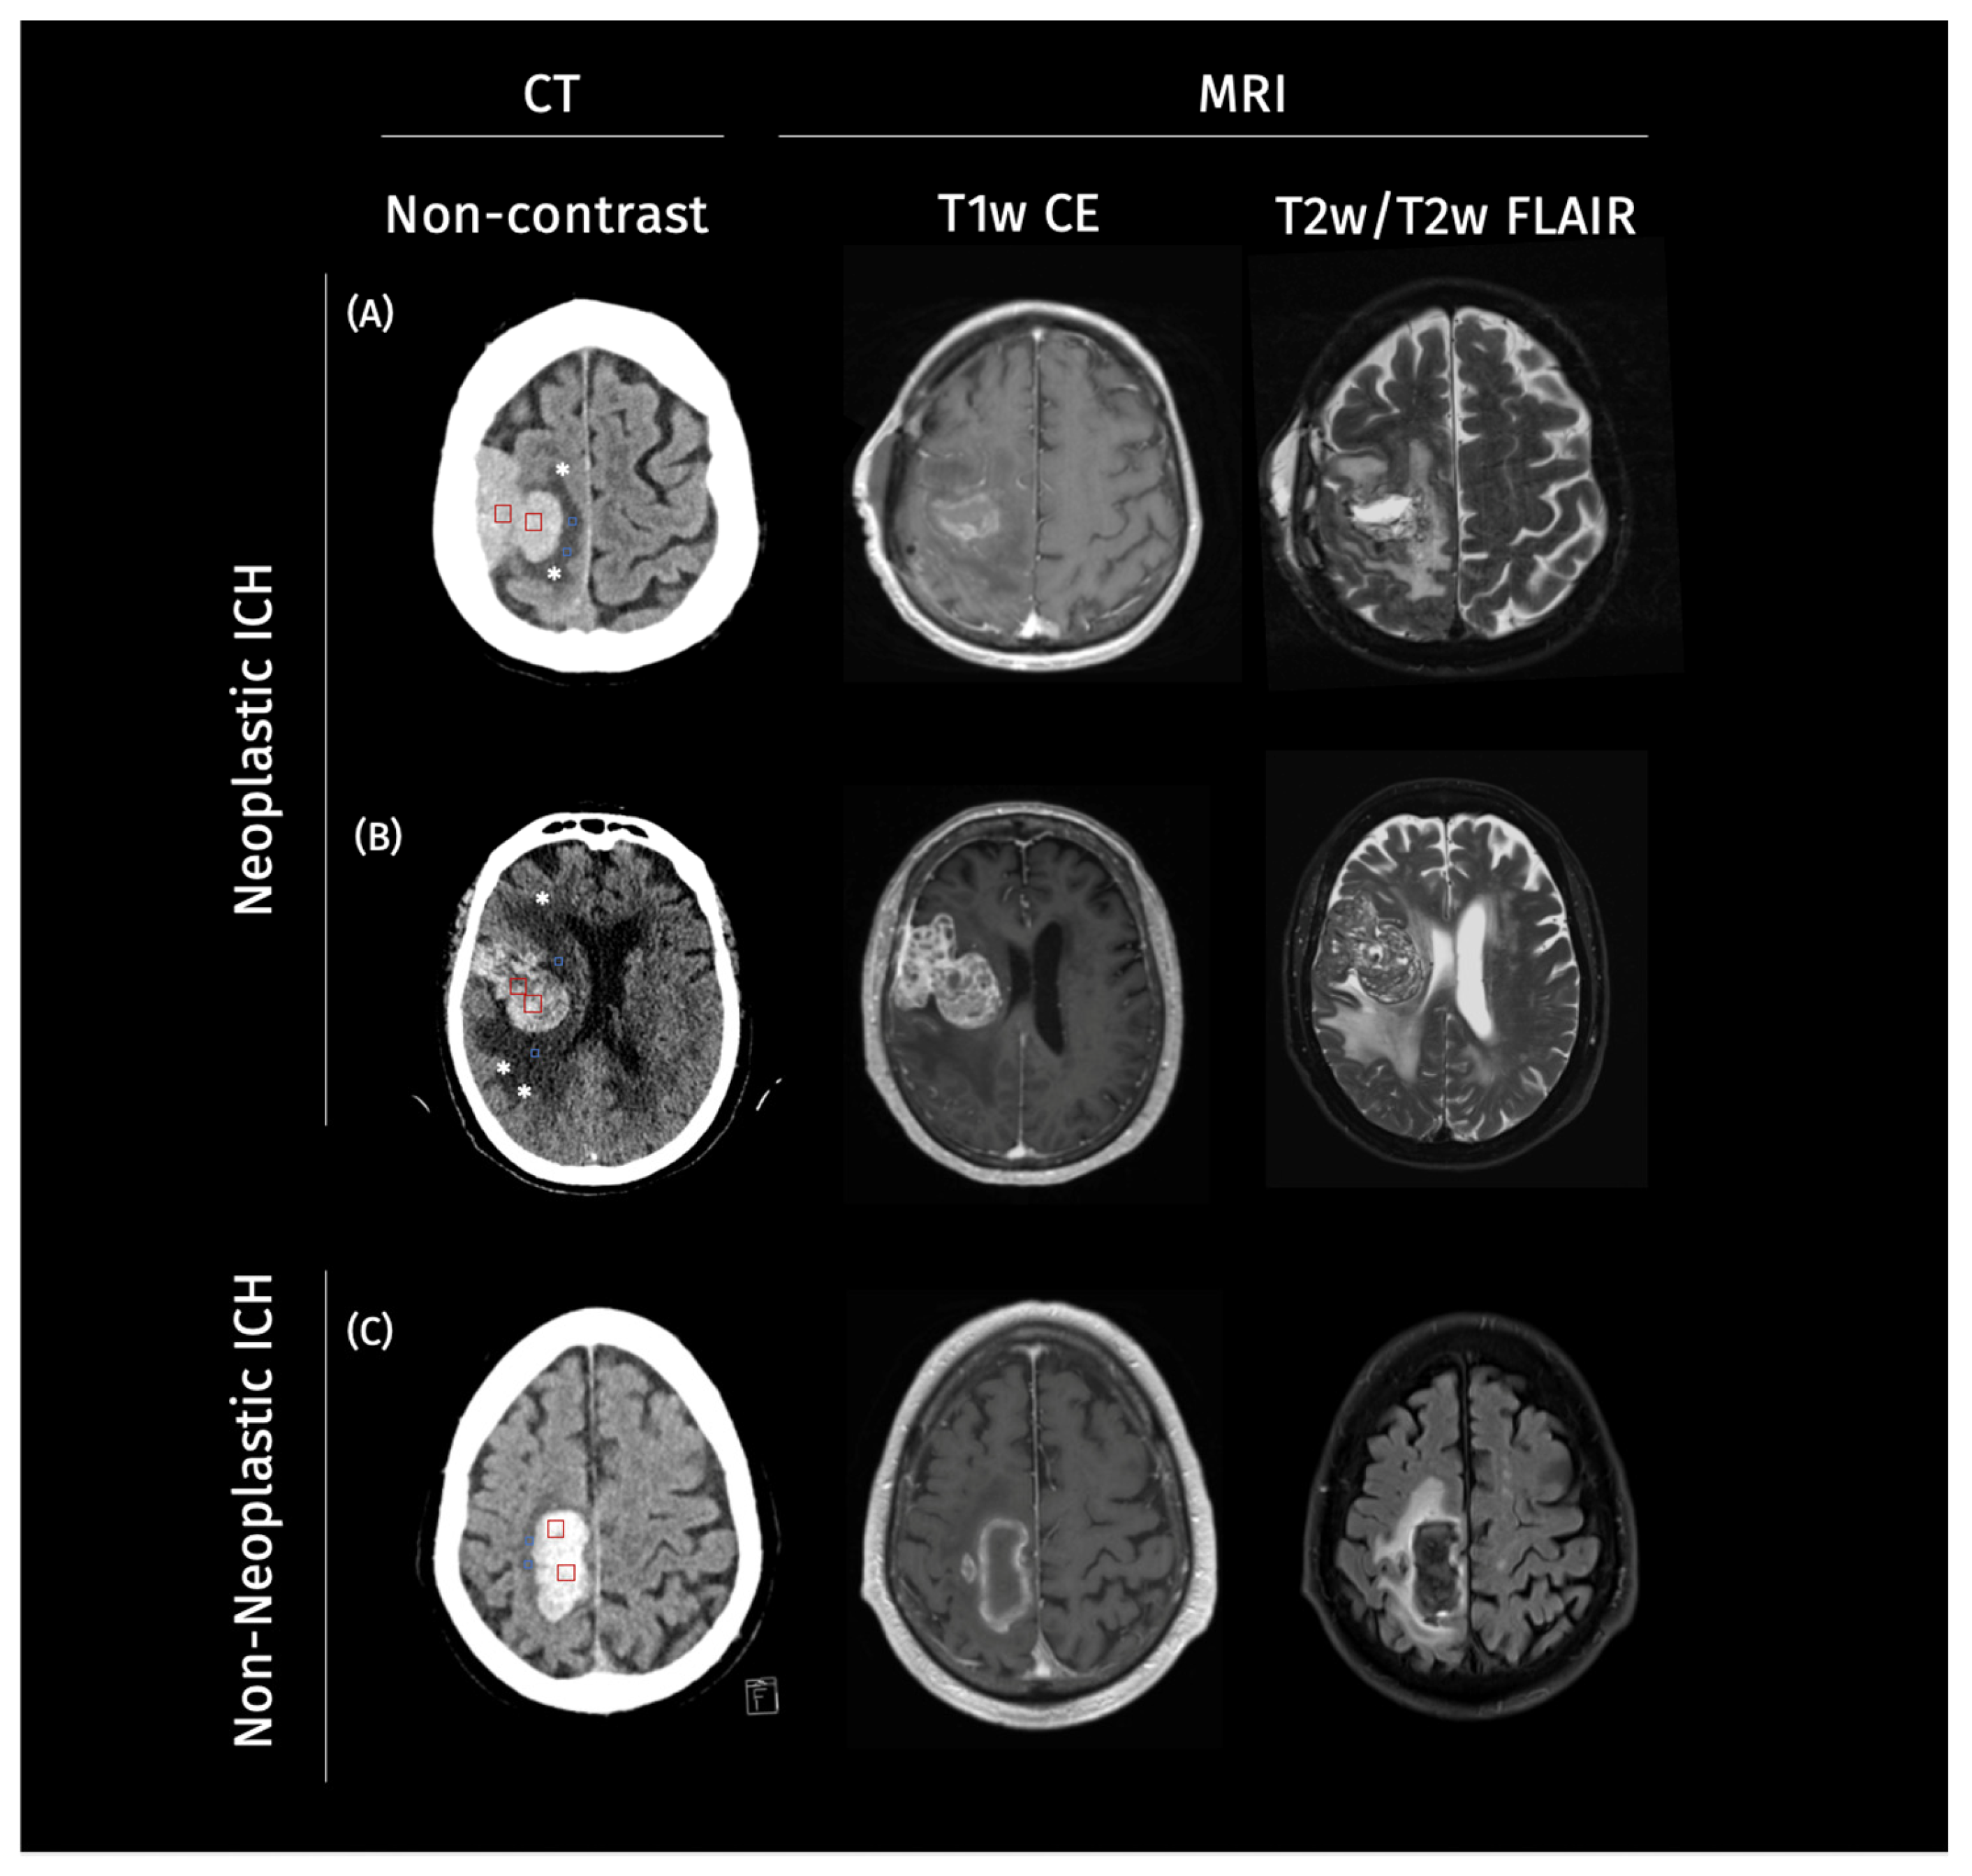

- Eminovic, S.; Orth, T.; Dell’oRco, A.; Baumgärtner, L.; Morotti, A.; Wasilewski, D.; Guelen, M.S.; Scheel, M.; Penzkofer, T.; Nawabi, J. Clinical and imaging manifestations of intracerebral hemorrhage in brain tumors and metastatic lesions: A comprehensive overview. J. Neuro-Oncol. 2024, 170, 567–578. (In English) [Google Scholar] [CrossRef] [PubMed]

- Nawabi, J.; Hanning, U.; Broocks, G.; Schön, G.; Schneider, T.; Fiehler, J.; Thaler, C.; Gellissen, S. Neoplastic and non-neoplastic causes of acute intracerebral hemorrhage on CT: The diagnostic value of perihematomal edema. Clin. Neuroradiol. 2020, 30, 271–278. [Google Scholar] [CrossRef]

- Nawabi, J.; Orth, T.; Schulze-Weddige, S.; Baumgaertner, G.L.; Tietze, A.; Thaler, C.; Penzkofer, T. External validation of the diagnostic value of perihematomal edema characteristics in neoplastic and non-neoplastic intracerebral hemorrhage. Eur. J. Neurol. 2023, 30, 1686–1695. [Google Scholar] [CrossRef]